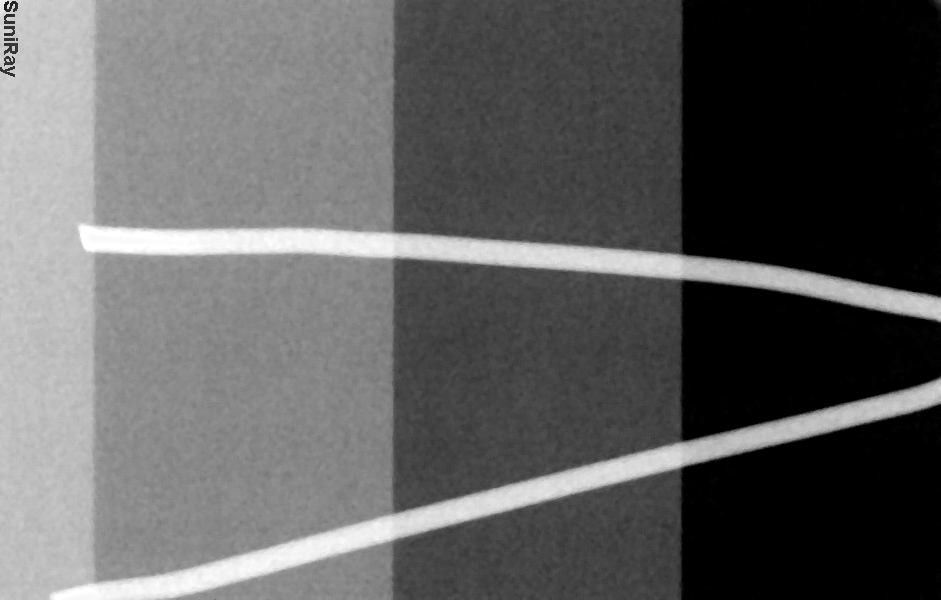

Please view the x-rays attached to this sensor before purchasing. Pre-Owned sensors may have imperfections in the image e.g. line, ghost image, dead pixels, or noise. Please ensure the image quality meets your standards.

Pre-Owned sensors may have artifacts in the image, please review the example images provided that were taken from the sensor prior to its sale. Tube heads or choice of exposure will affect the contrast, brightness and clarity of the image. Sodium Dental is not responsible for this. Any return of product will be subject to a 15% restocking fee and no refund of shipping.